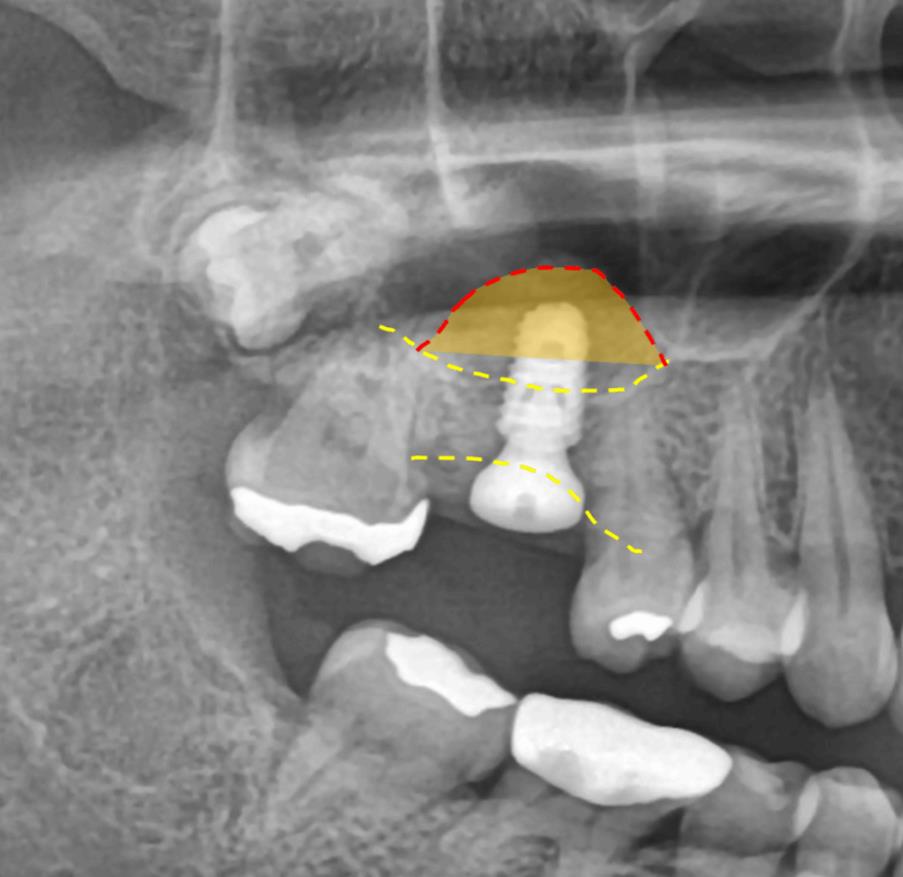

수술 전 파노라마 – 상악동과 인접한 위치 확인

수술 전 CT – 뼈 높이가 부족해 상악동 거상술 필요 소견